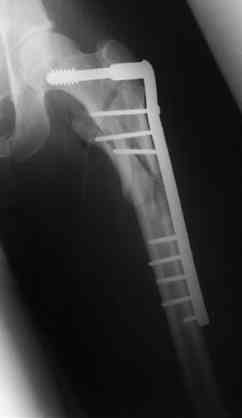

Вчера прооперировал больного.

Попытка низвести половину таза на тракционном столе ( скелетное вытяжение за бедро) безуспешная.

из переднего доступа добрался до правого КП сочленения , все запаяно костью, с помощью 2 шанцев винтов в крестец и подвздошную кость и элеватора репозиция, контроль ЭОП

и двумя пластинами фиксация.

Спереди, аппарат как рекомендовал Джолдас.

Снимки плохого качества( очень темные) завтра переделают и пришлю на конференцию.

На мой взгляд, смещение устранено и фиксация выглядит вполне анатомичной.

В приложении послеоперационные картинки.

Всего доброго,

Спасибо всем принявшим участие в обсуждении,

Чекашкин Е.И.